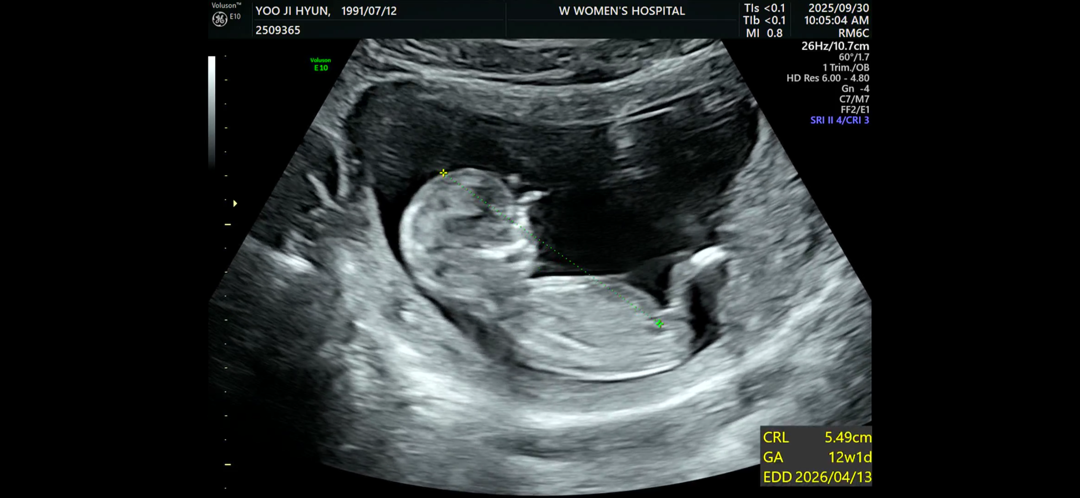

12주 4일차 각도법 문의

각도법 문의드립니다 투표 감사합니다~!!